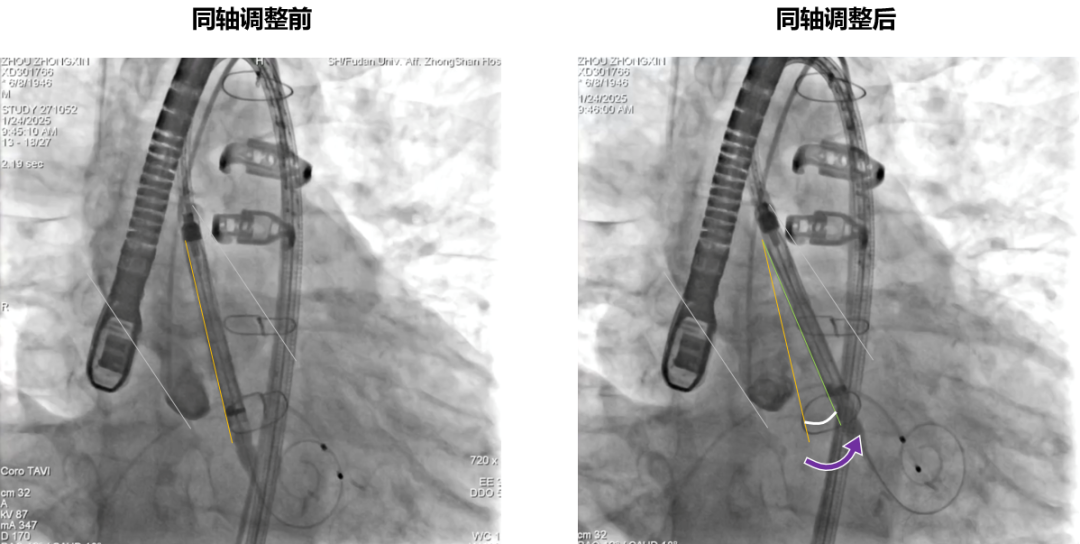

跨瓣后同轴调整

同轴调整前后对比

患者在全麻下进行手术,经右侧股动脉建立主入路,直头导丝跨瓣后交换预塑弯形导丝放置于左室。TaurusMax®经导管主动脉瓣系统装载AV29瓣膜,该系统具有“双轴”调弯功能,系统过弓跨瓣更加安全顺畅,同时系统在跨瓣后可实现同轴调整,降低术中对导丝操作的依赖,改善瓣膜释放不同轴导致的高低瓣问题,提升瓣膜释放稳定性及血流动力学。瓣膜在调弯状态下一次释放脱钩,瓣膜深度瓣下2mm,形态良好,同轴性佳,DSA下对合缘对齐(CA)结果良好。